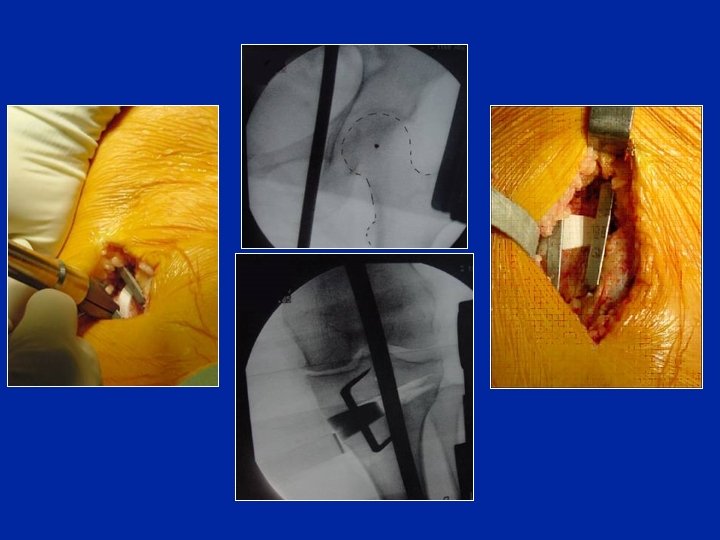

1 - Ostéotomie d’ouverture • Autogreffe (iliaque) • Allogreffe (tête fémorale • Substitut osseux

Contrôle opératoire Contrôle radioscopique Une tige matérialisant le tibia doit passer en dedans de la tête fémorale (30 à 40 mm) 1° = 7 à 8 mm 1 - Appliquer les 2 compartiments 2 – contrôler en faisant du varus forcé

Contrôle opératoire de la correction 35 mm 5° = 35 mm On peut matérialiser le centre du fémur par un répère métallique placé sur la peau sous radioscopie, ainsi qu’un autre répère correspondant au but à réaliser Préop On peut les percevoir sous les champs opératoires Postop

Correction correcte Hypercorrection excessive